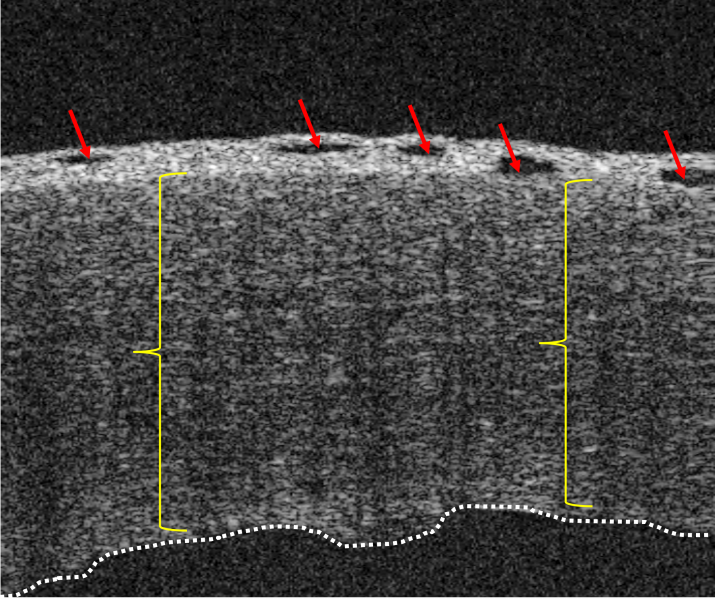

Pseudophakic bullous keratopathy (PBK): Anterior segment OCT image showing hallmark features of pseudophakic bullous keratopathy (PBK). Red arrows indicate epithelial bullae. Yellow brackets highlight diffuse stromal thickening consistent with corneal edema. The dotted white line outlines the posterior corneal surface, representing the irregularity of the endothelial layer of the cornea. (image courtesy of Joobin Khadamy, MD, FEBO)